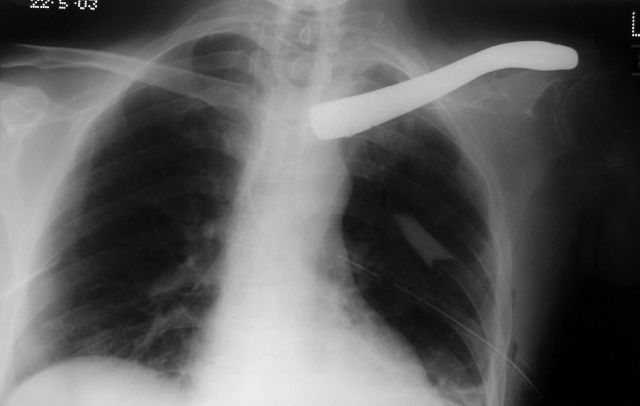

Before the operation the right hand side clavicle can be clearly seen on this x-ray, and below that the post-operative x-ray clearly shows the titanium implant.